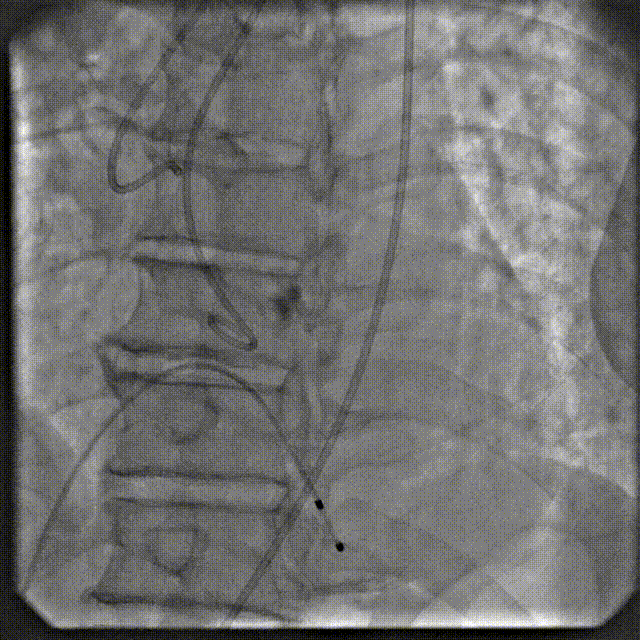

在数字减影血管造影(DSA)与经胸超声(TTE)双模影像引导下,学员系统完成经导管主动脉瓣置换术全流程操作:首先建立经皮腹主动脉穿刺入路,随后进行导丝跨瓣定位,继而操控人工瓣膜输送系统,最终实现瓣膜精准释放。训练重点强化三个技术维度:①血管入路建立与并发症预防 ②影像引导下的器械递送路径规划 ③基于实时超声的血流动力学评估。